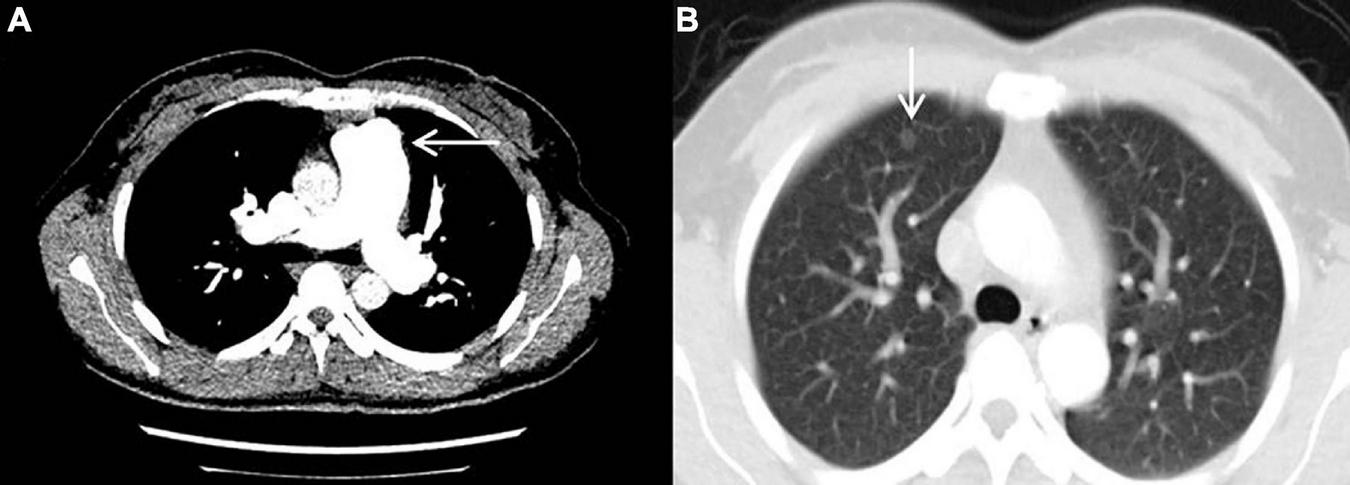

The result of right heart contrast echocardiography was consistent with pulmonary arteriovenous malformations (AVMs). The result of echocardiography was indicative of pulmonary hypertension (PH). Electronic gastroscopy showed chronic non-atrophic gastritis but no gastric vascular malformations. Pulmonary function showed mild diffusion dysfunction. No obvious filling defect or vascular malformations were observed on CTPA (Figure 2A), but several ground-glass opacities were seen on the lung window of CTPA, where one of 7.8 mm × 7.5 mm in diameter was located in the right upper lung lobes (Figure 2B). The result of right heart catheterization (RHC) is shown in Table 2. Pulmonary angiography showed AVMs of the left upper pulmonary artery (Figure 3A), and anterior cerebral artery malformation was seen in cranial computed tomographic angiogram (Figure 3B). Genetic testing revealed the patient carried heterozygous variants in the ENG c.1195-1196del p.Arg399GlyfsTer2. Except her son, all her three daughters carried a heterozygous variant at the ENG c.1195-1196del locus.

Figure 2. Computed tomography pulmonary angiography. (A) No obvious filling defect or vascular malformations were observed. (B) The ground-glass opacity that was 7.8 mm × 7.5 mm in diameter and located in the right upper lung lobes was seen.